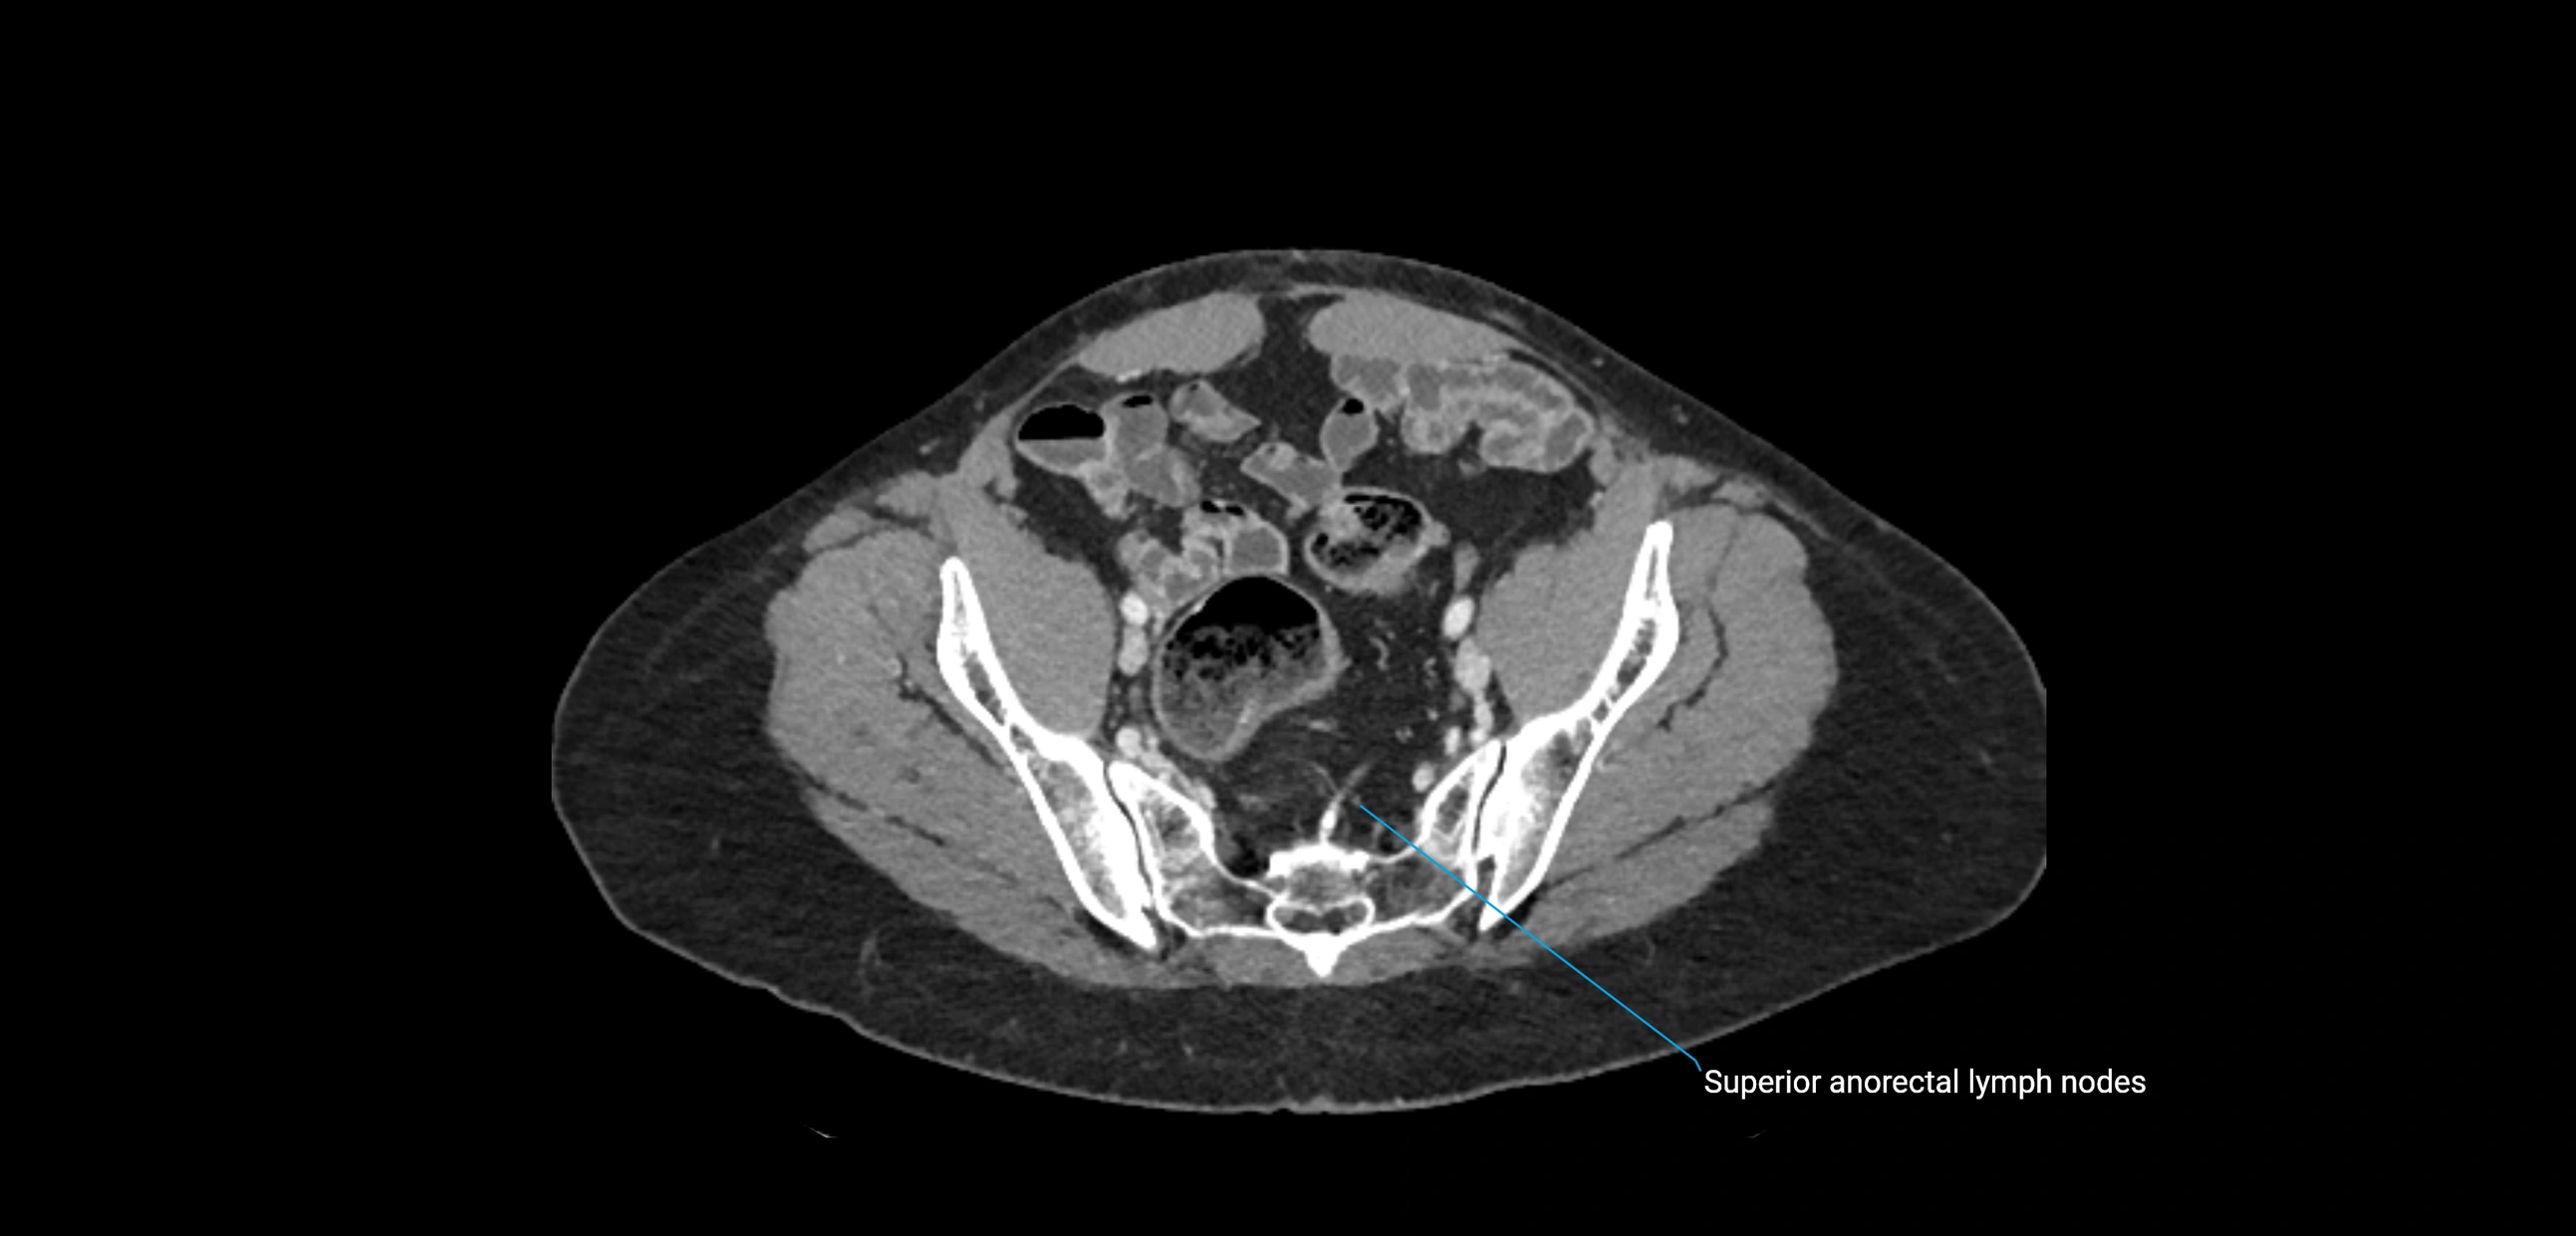

These nodes receive lymph from a wide range of abdominal and pelvic structures. Specifically, they drain lymph from the kidneys, suprarenal glands, gonads (testes/ovaries), uterus, uterine tubes, and pelvic organs, before converging into the lumbar lymphatic trunks, which terminate in the cisterna chyli → thoracic duct.

Clinically, the lateral aortic lymph nodes are critically important in oncology, being involved in the spread of testicular cancer, ovarian cancer, endometrial cancer, cervical cancer, renal malignancies, and retroperitoneal lymphomas. They are also key targets in retroperitoneal lymph node dissection (RPLND) for testicular tumors.

CT Appearance

CT Post-Contrast:

• Normal nodes enhance homogeneously

• Malignant nodes may show heterogeneous enhancement, central necrosis, or conglomerate formation

• Size >1 cm short axis is suspicious, though morphology and distribution are equally important